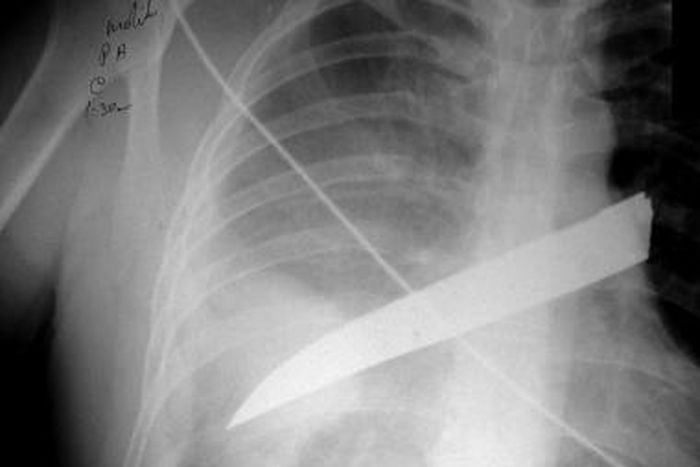

The victim makes it to the hospital with the blade firmly placed in her back. It is an outcome of many acts of violence against the sister who is positioned on a sick bed captured on social media.